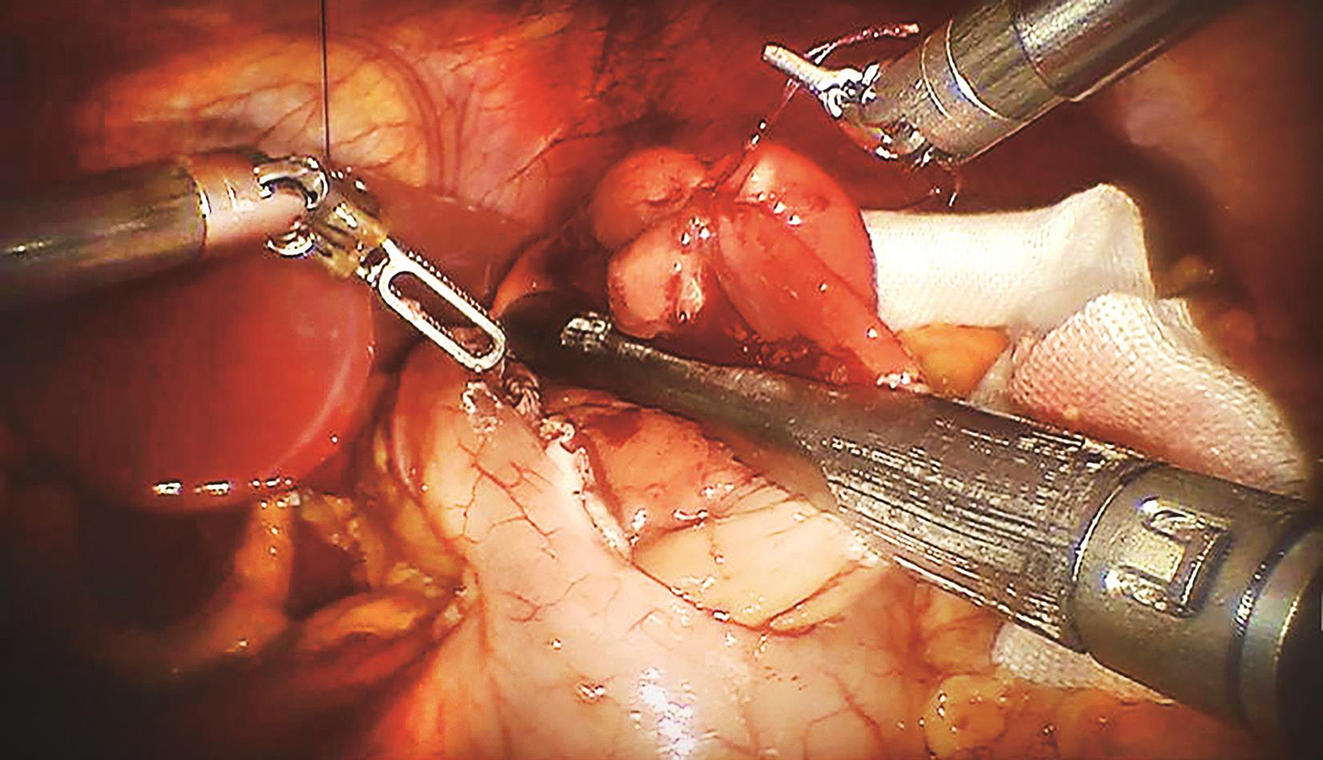

患者于加速康复外科(enhanced recovery after surgery,ERAS)理念指导下行术前准备,2016年9月27日行“机器人辅助下腹腔探查术+胃肿瘤切除术”。术中先行胃镜探查发现肿瘤位于胃底后壁近贲门处,大小约2.0cm×1.0cm;离断大弯侧网膜,暴露胃后壁瘤体,切开后壁肿瘤所对应胃前壁,以腹腔镜下切割吻合器于距离瘤体1cm处离断胃壁,完整切除肿瘤,将肿瘤置入标本袋中并用丝线结扎袋口,经绕脐半周切口取出,检查标本切缘安全,以可吸收线加固切口,缝合腹部戳孔及绕脐切口。手术过程顺利,手术时间60min,术中出血量约为10ml(图2~图5)。

图4 切割吻合器切除肿瘤

图5 3-0可吸收线缝合胃壁